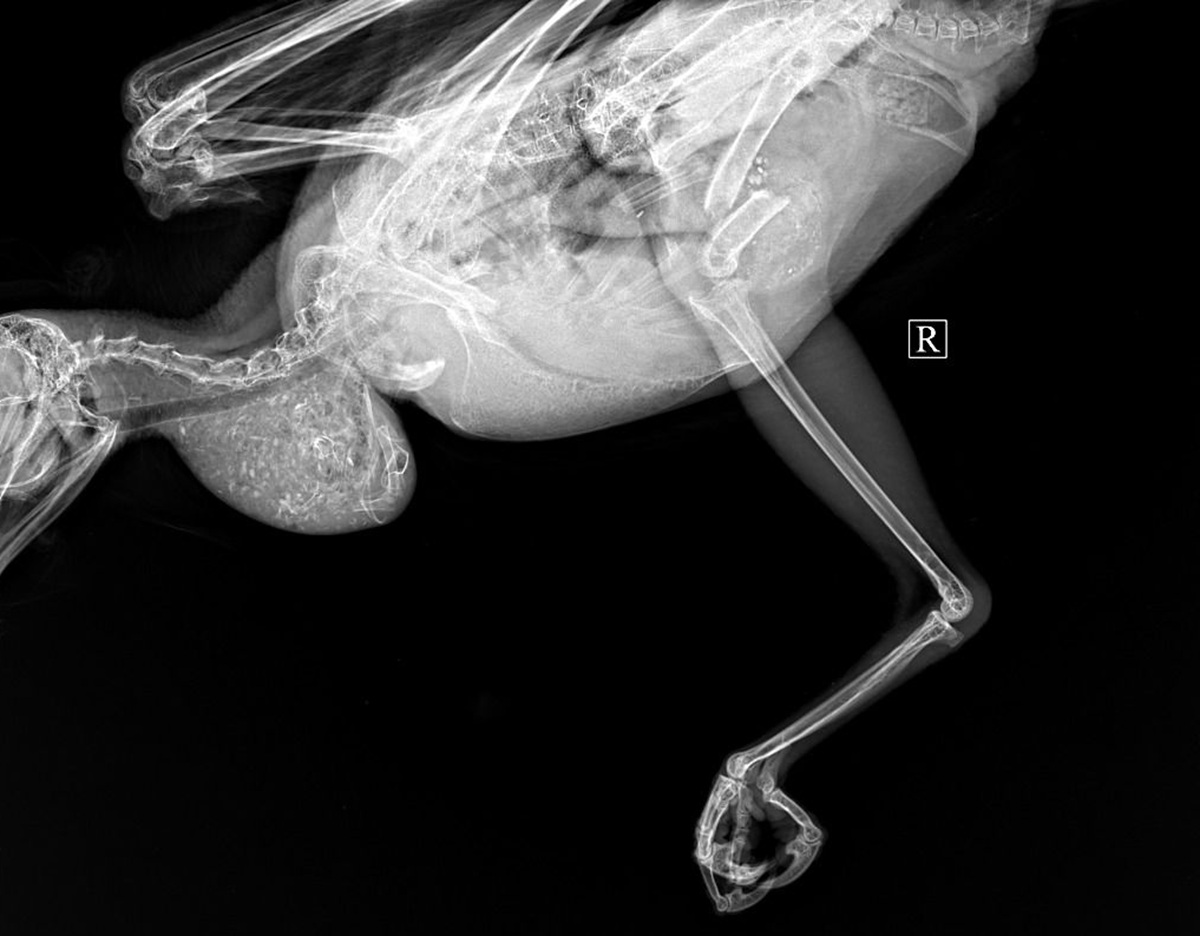

Так, врачи-орнитологи проводят лечение и полноценную реабилитацию диких хищных птиц, поступающих с тяжёлыми травмами, в том числе с переломами крыльев и конечностей.

По словам специалистов, в клинике уже были проведены операции на конечностях, казалось бы, безнадёжных крылатых пациентов.

Благодаря точной диагностике, хирургическому вмешательству и качественной реабилитации многие пернатые уже вернулись в дикую природу. Один из спасённых беркутов был передан для содержания на страусиную ферму, - рассказали ветеринары.

Специалисты рассказали, что при операциях на диких хищных птицах особенно важно минимизировать риски, так как они крайне чувствительны к наркозу. Для этого необходима газовая анестезия, которая считается наиболее безопасной, но при этом является дорогостоящей.